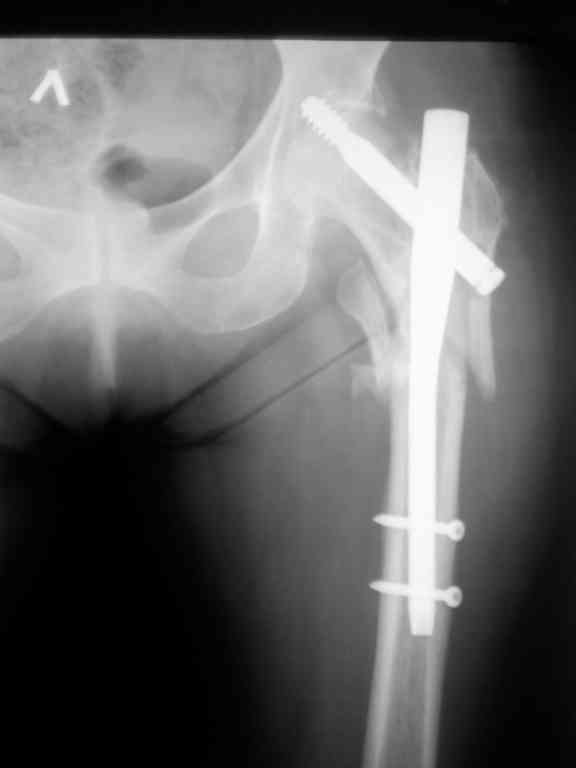

Больная С. 1945 г.р. Диагноз при поступлении чрезвертельный перелом левого бедра. Операция остеосинтез бедра гамма стержнем в январе 2010. Ведение больной в послеоперационном периоде активное, с марта больная ходит с тростью. Жалоб активно не предъявляла. В июне 2010 появились боли в левом паху и тазобедренном суставе. При контрольной ретгенографии в июле 2010 определяется миграция винта в вертлужную впадину. Рис.1.